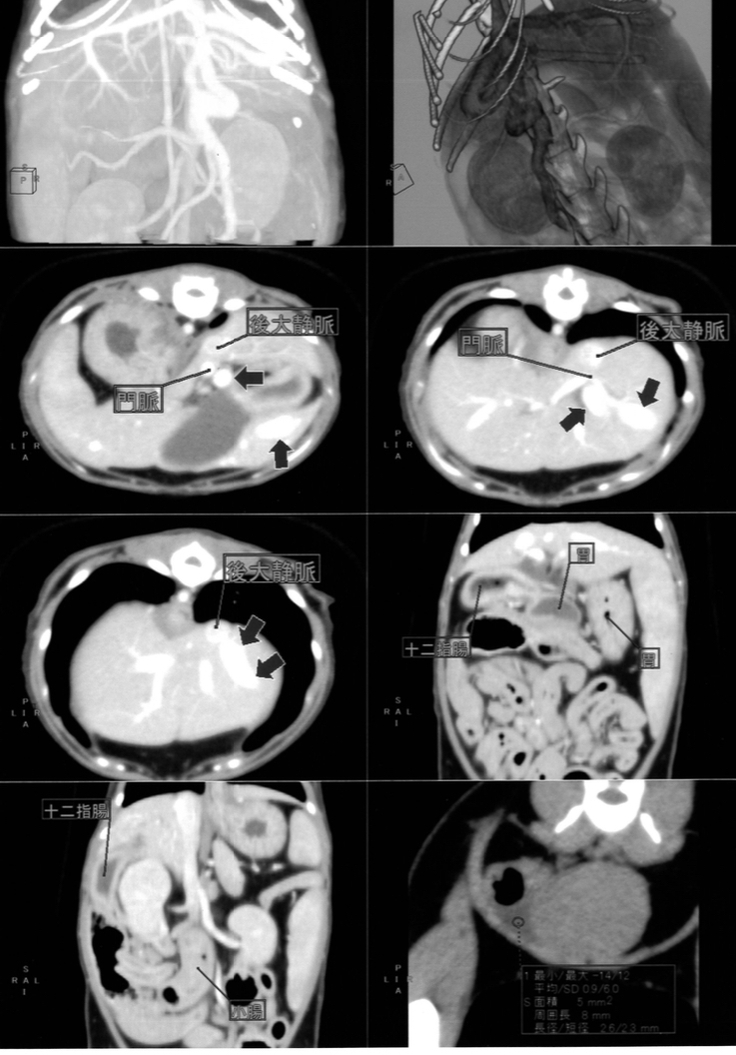

転院先の病院で造影剤CTを受ける。

検査の結果、門脈シャントであることが確定。シャントが太く難しい場所にあり、十二指腸の腫れ、腹水も認められる。太いシャントの場合は、一度に血管を閉鎖すると一気に門脈血流が増加することで症状が悪化するため、複数回に分けて手術が必要になる可能性があるとの説明がある。肝臓に疾患があり麻酔薬を分解できないためCT時の麻酔ですらなかなか目覚めず、門脈シャントの開腹を伴う手術の麻酔に体が耐えられない可能があるとのこと。しかし内科的治療だけでは数ヶ月~数年の延命しか望めないため、手術成功に望みを託して手術をお願いする

造影剤CT画像

肝臓に入っていくはずの血管が違う場所に繋がっています

しかもかなり太いそう